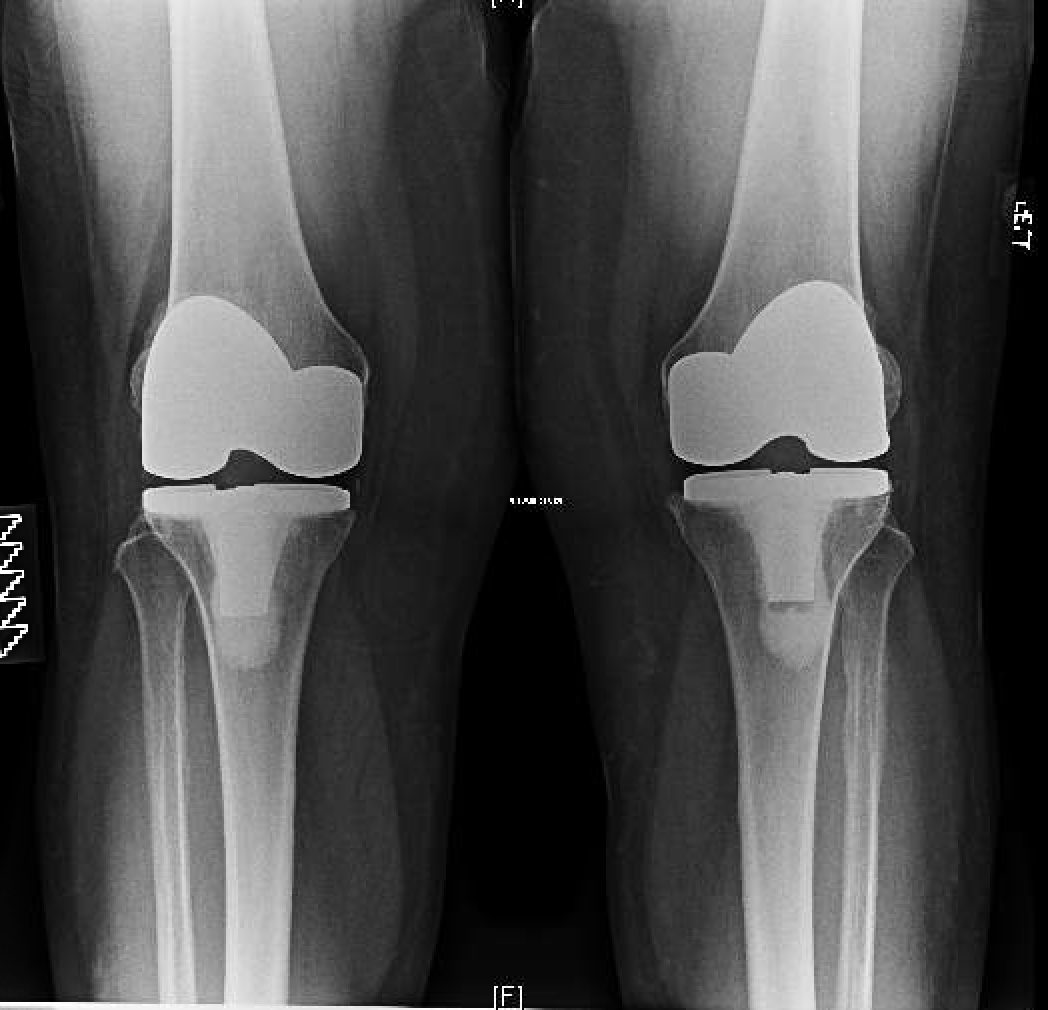

BILATERAL KNEE REPLACEMENT

"Enjoying Every Minute of It"

After many years of discomfort with both knees, endless amounts of injections, and getting nowhere I met Mr Vioreanu at the Sports Surgery Clinic in December 2014.